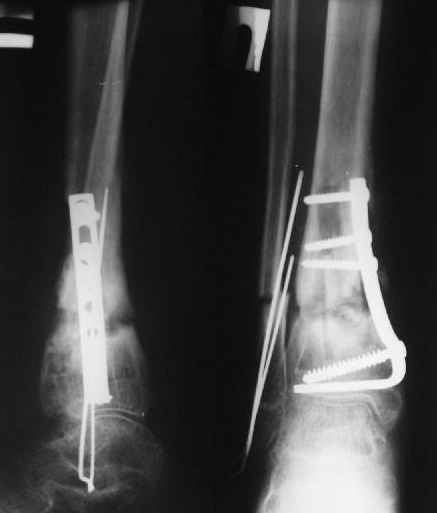

Уважаемые коллеги!Поступила пациентка 40лет, псевдоартроз Н/3 большеберцовой кости, оперирована 1,5-а года назад по поводу перелома ПИЛОНА в Австрии, травма горнолыжная.

после остеосиннтеза |  05.07.04 |  12.04.05 | Пластина удалена через 4-е месяца (миграция винтов), полимерная повязка на 2-а мес. Беспокоит деформация голени,укорочение 1-1,5см, боли незначительные, движения в г/стопном суставе в полном объёме, ходит с полной нагрузкой на ногу, подвижность в переломе не определяется. Одномоментное исправление деформации, костная пластика (chronOS)+ пластина? Аппаратная коррекция, затем пластина? Аппарат? Прошу Ваших советов. С Уважением А.Миронов

Ситуацию, похоже, можно трактовать как тугой ложный сустав. Отсюда и тактика - поскольку тугие псевдартрозы успешно лечатся стабилизацией/дистракцией, здесь вполне годится лечение аппаратом.

Остеотомия малоберцовой кости в нижней трети (плоскость выбрать так, чтобы не мешать ее тенденции занять более правильное положение по отношению к сустаному концу большеберцовой кости), зафиксировать обе кости 1-2 спицами, наложить аппарат (еще 3-4 спицы с упорами в дистальный блок, спицы или стержни в диафиз) с шарнирами, ось

которых должна проходить чуть кзади от вершины деформации. Далее - небыстрая дистракция, дней за 10 устранить угол. Стопу фиксировать не надо.

Здесь есть основания рассчитывать на сращение в течение нескольких месяцев, поэтому мотивация к переходу на внутреннюю фиксацию невысока.

Что касается пластики и пластины - может сработать, но с полной нагрузкой придется сильно повременить (в аппарате можно не прекращать). А также инфекция и нестабильность внутреннего и внешнего фиксатора будут иметь разную "стоимость".